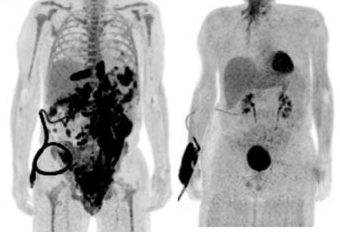

Chimeric Antigen Receptor T-cell (CAR-T) therapy is a revolutionary approach cancer treatment. T cells extracting a chimeric antigen receptor (CAR) that targets specific cancer cells can destroy cancer cells while sparing healthy cells. CAR-T was successfully used to treat certain aggressive blood cancers. Within 28 days of the CAR-T cell therapy, 50 percent of patients responded positively and around 80% to 90% of patients will go into remission after six months (Terry Fry, 2024, Massimo Martino et al, Front. Immunol., 02 May 2024). With the recent progress in automated CAR-T cell manufacturing facility the preparation of cells to be infused back into a patient can be ready within 14 days.

Six FDA-approved CAR T cell treatments are available, including the pioneering CRISPR-based clinical trials for treating sickle cell disease and beta-thalassemia.

Photo Medical College of Wisconsin, Oct 5th, 2020